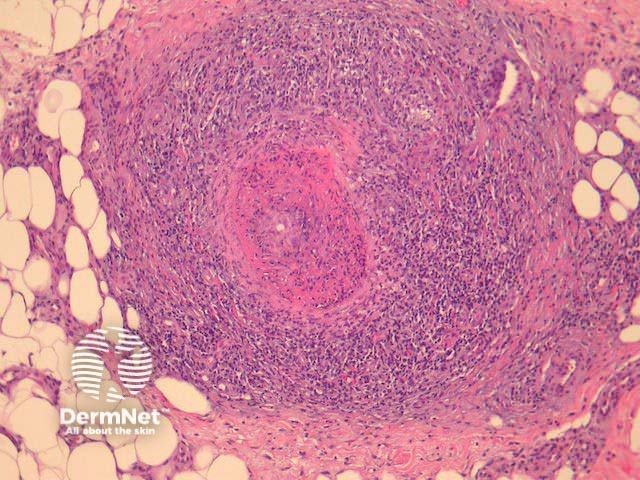

Histological features of systemic and localised cutaneous forms of polyarteritis nodosa are similar. A deep biopsy is preferred as cutaneous polyarteritis nodosa involves medium-sized vessels in the deep dermis and subcutis (Figure 1). Early lesions show fibrinoid necrosis with thickening and infiltration of the vessel wall. Neutrophils, eosinophils and lymphocytes are present (Figures 2,3). Leucocytoclasis may be present. Thrombi and aneurysmal change may occur and lead to necrosis of the overlying epithelium. In mature lesions vessel occlusion occurs secondary to intimal and mural fibrosis. Lesions at various stages are characteristic and changes are discontinuous with uninvolved skip lesions between affected segments.

Figure 1